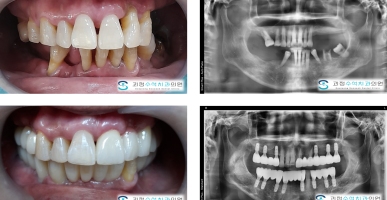

라미네이트 + 오래된 보철(크라운)교체

앞니의 오래된 보철(크라운)을 새로운 지르코니아 크라운으로 교체하고 라미네이트를 병행한 사례입니다.